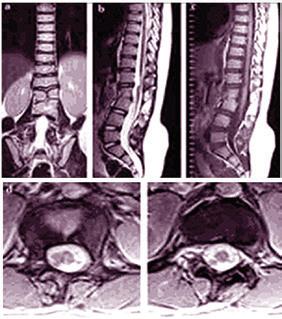

By Sarah Toatley

ctober brings a sea of pink, and a timely reminder of the importance of breast health. Breast Cancer

Awareness Month is not just about honoring survivors and advancing research; it’s also about taking action for your own health. Whether you’re due for your first mammogram, have questions about changes in your cycle, or want guidance through menopause, your provider is here to help. Breast health is lifelong health, start the conversation today.

Martha Moe, MD, medical director of the Center for Women’s Health at South County Health, has spent her career guiding women through all stages of life, from early adulthood to post-menopausal. She emphasizes that breast health is just one part of the larger picture of caring for yourself, and that open conversations with a trusted health provider can lead to healthier, longer, and fuller lives. We sat down with Dr. Moe to talk about the importance of mammograms, the value of proactive care, and how women can seek the support they need through every season of life.

Why are regular mammograms so important?

Dr. Moe: Mammograms are still the single best screening tool we have for early detection of breast cancer. When caught early, treatment options are more effective, less invasive, and survival rates are significantly higher. It is important for patients to understand that getting a mammogram is like setting a safety net in place for your health; you hope you never need it, but it’s there to protect you. For most women, screening begins at age 40, but personal risk factors – such as family history or dense breast tissue – may mean you should start sooner. The key is having the conversation with your provider so your screening plan is tailored to you.

Some women avoid screening mammograms out of fear or discomfort. How do you help them overcome that?

Dr. Moe: We understand that mammograms can spark fear in some patients, which is normal. Yet it shouldn’t create a barrier between you and your health. Mammograms are quick, usually under 20 minutes, and the peace of mind they bring can far outweigh the temporary discomfort during the exam. At South County Health, we strive to create a calm, respectful environment where patients feel heard, cared for, and not rushed.

Your expertise covers women’s health beyond breast cancer. What are some key milestones when women should be especially proactive?

Dr. Moe: Breast health is one piece of a much larger journey, because each stage of life comes

with unique needs. Some patients at one point in life might be dealing with heavy or painful periods or other symptoms from fibroids or endometriosis, which can be life-altering conditions. Other patients are navigating reproductive health choices and pregnancy, or dealing with pelvic floor changes or even perimenopause or menopause. Health care is not one-size-fits-all, and it is constantly evolving over the course of a woman’s life. By maintaining a relationship with your provider, we can navigate changes early and support you in ways that are right for your life stage.

What role does support play in women’s health?

Dr. Moe: Support is everything in women’s health. That might be your partner, family, friends, or even a care team that listens

“Preventive

MARTHA MOE

without judgment. When women have a safe space to voice concerns – whether about breast lumps, irregular cycles, or symptoms of menopause – they’re far more likely to seek care early and follow through with treatment. We encourage women to build that support network and to use us as a trusted resource. You never need to face these decisions alone.

If you could share one message during Breast Cancer Awareness Month, what would it be?

Dr. Moe: Your health is worth prioritizing, always. You don’t need to wait until something feels wrong to make an appointment. Preventive care is a gift you give to yourself and your loved ones, and scheduling an annual mammogram is easy. Walk-In appointments are available at our East Greenwich, Wakefield, and Westerly locations, and no provider order is necessary for an annual mammogram.